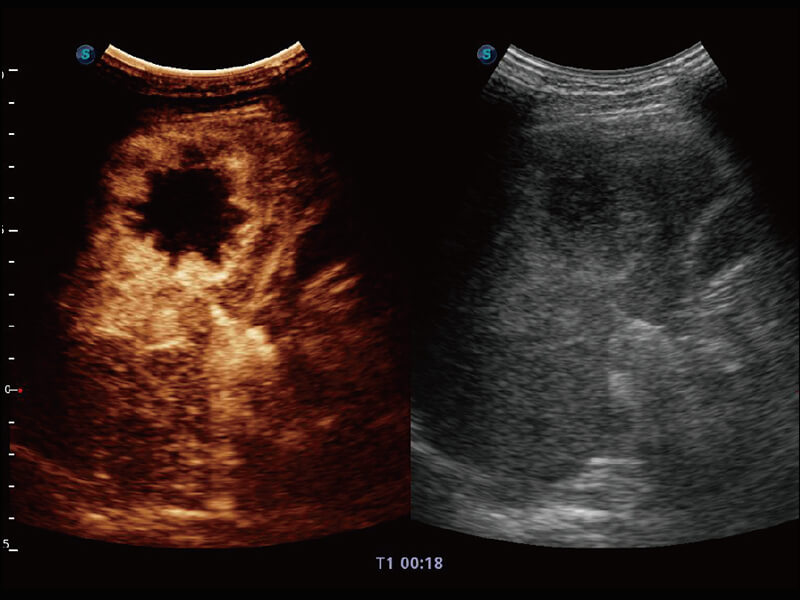

S60探头工艺,从前端信号处理每一个环节采集无损声学数据,真实还原组织原貌,再现解剖细节。

• 腹部单晶体探头( C1-6A )

Micro F 显微血流成像 明察秋毫